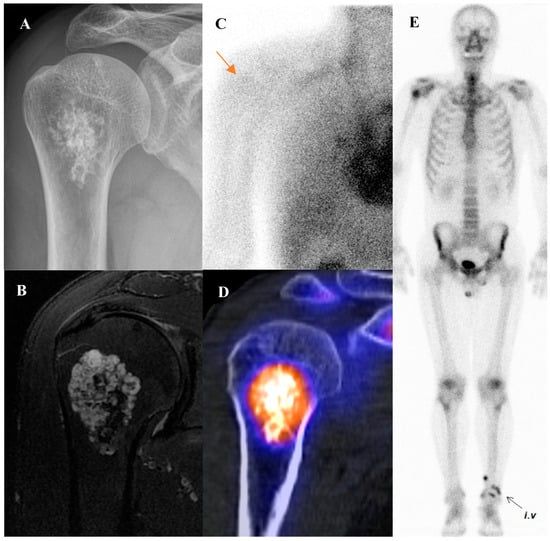

Perhaps the most critical role for [18F]FDG PET/CT in osteosarcoma management is in the evaluation of response to neoadjuvant chemotherapy. The standard of care for high-grade osteosarcoma involves preoperative chemotherapy followed by surgical resection. The degree of tumor necrosis in the resected specimen is one of the most powerful prognostic factors. A “good response,” defined as ≥90% tumor necrosis, is associated with a much better prognosis than a “poor response” (<90% necrosis). [18F]FDG PET/CT perfor-med before and after neoadjuvant chemotherapy can non-invasively predict this histologic response. A significant reduction in the tumor’s SUVmax following chemotherapy is a robust indicator of a good pathologic response [15,37,38,39,40,41,42,43]. This information can help predict prognosis and guide critical therapeutic decisions. Figure 1 demonstrates a representative case in which marked reduction of [18F]FDG uptake after chemotherapy corresponded to predominantly necrotic tissue in the resected specimen, resulting in long-term disease-free survival. This information can help predict prognosis and guide critical therapeutic decisions.

Figure 1.

A 16-year-old male with osteosarcoma of the right distal femur. (A) Pretreatment bone scintigraphy shows intense uptake in the distal femoral metaphysis. (B,C) Pretreatment [18F]FDG positron emission tomography/computed tomography demonstrates a heterogeneous, [18F]FDG-avid mass with cortical breakthrough and soft-tissue extension (SUVmax 12.6). (D,E) After neoadjuvant chemotherapy, [18F]FDG uptake markedly decreased (SUVmax 2.3) with reduction in tumor extent. (F) Wide excision specimen (×40) revealed predominantly necrotic tissue, confirming a marked response to chemotherapy, in contrast to (G) the pretreatment biopsy specimen (×100) with viable malignant cells. He has remained disease-free for 8 years.